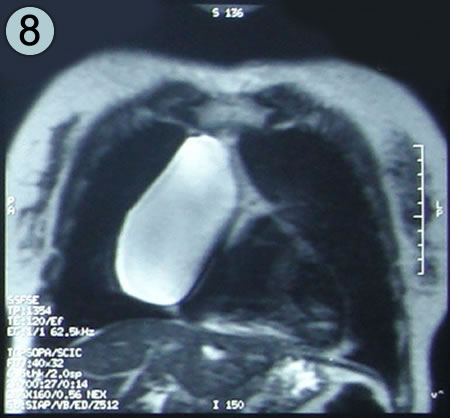

Corte Axial en secuencia T1

Corte mediastinico paracardiaco.

Inmediatamente por debajo o distal a la lesión, imagen cardiaca luce un pericardio de aspecto normal.

la lesión redondeada ya no es visible.